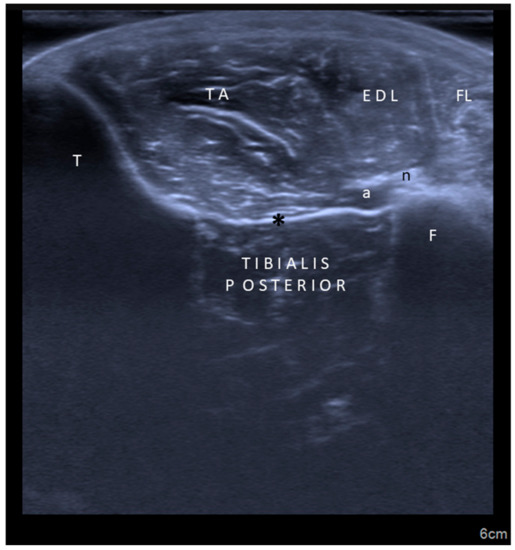

Second, concerning particular muscles, we strongly disagree with the authors regarding tibialis posterior, iliopsoas, and sternocleidomastoid injections. In the former two muscles, the innervation zones are well known to be localized much more proximal [,,], necessitating injections accordingly (Figure 1 and Figure 2). For the latter one, again based on the evidence of innervation zone distribution, latero-medial rather than cranio-caudal injection would be crucial (Video 1). Yet, the innervation zones are shown to be arranged perpendicular to the muscle fibers [].

Figure 2.

Ultrasound imaging (axial view) for tibialis posterior muscle. TA: Tibialis anterior; T: Tibia; F: Fibula; EDL: Extensor digitorum longus; FL: Fibularis longus; a: Artery; n: Nerve; *: Interosseous membrane.